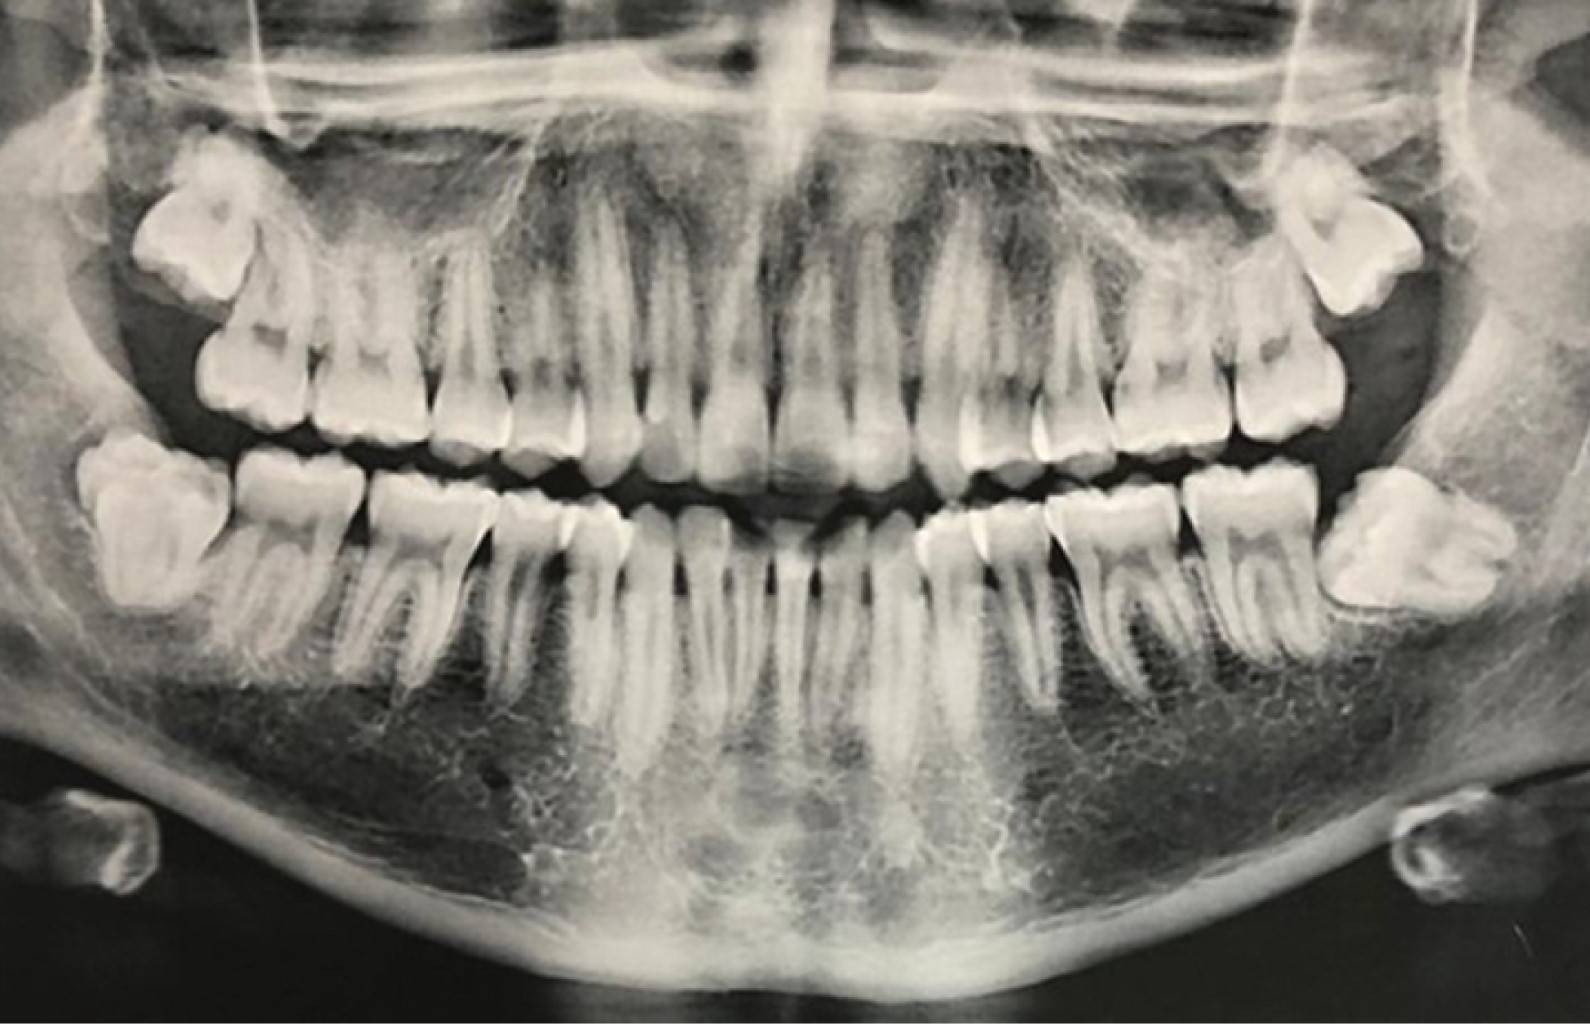

Caso 1. Varón de 16 años de edad, aparentemente sano, referido por ortodoncista para manejo quirúrgico preortodóntico por hallazgo radiográfico consistente en una posible fusión del tercer molar inferior derecho y un cuarto molar, ambos en desarrollo coronal (Figura 1). Destacó además agenesia del resto de los terceros molares. Se realizó odontectomía bajo anestesia local con técnica convencional, confirmando la fusión de estos órganos dentarios. El distomolar se encontraba fusionado en la superficie distal de la corona del tercer molar; sin embargo, éste último presentaba una giroversión mesial, por lo que el diente supernumerario estaba ubicado adyacente a la tabla ósea vestibular (Figura 2).